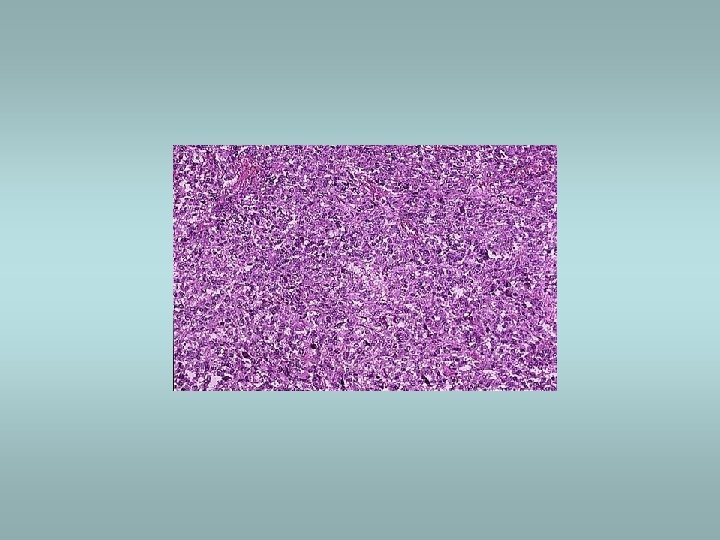

- Slides: 56